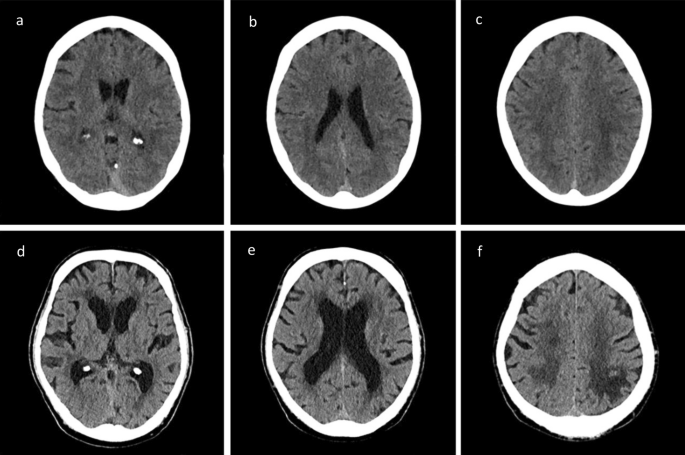

Image analyses of leukoaraiosis

The grade of LA was assessed using the 4-point van Swieten scale (vSS)15 in NCCT on admission (Fig. 1). The grading was performed by an experienced neuroradiologist and trained rate rafter multi-staged training process by an experienced neuroradiologist. In case of different results in grading, a result was found by consent. Some patients were transferred secondary from an extern hospital to our clinic. In most of these cases the NCCT was repeated on admission. If the NCCT was not repeated due to time constraint, we used the external NCCTs to evaluate the grade of LA. In some patients with massive early ischemic changes in NCCT and large contralateral stroke in history it was not possible to assess the severity of LA. LA was dichotomized in absent-to-mild (vSS 0–1) versus moderate-to-severe (vSS2-4).